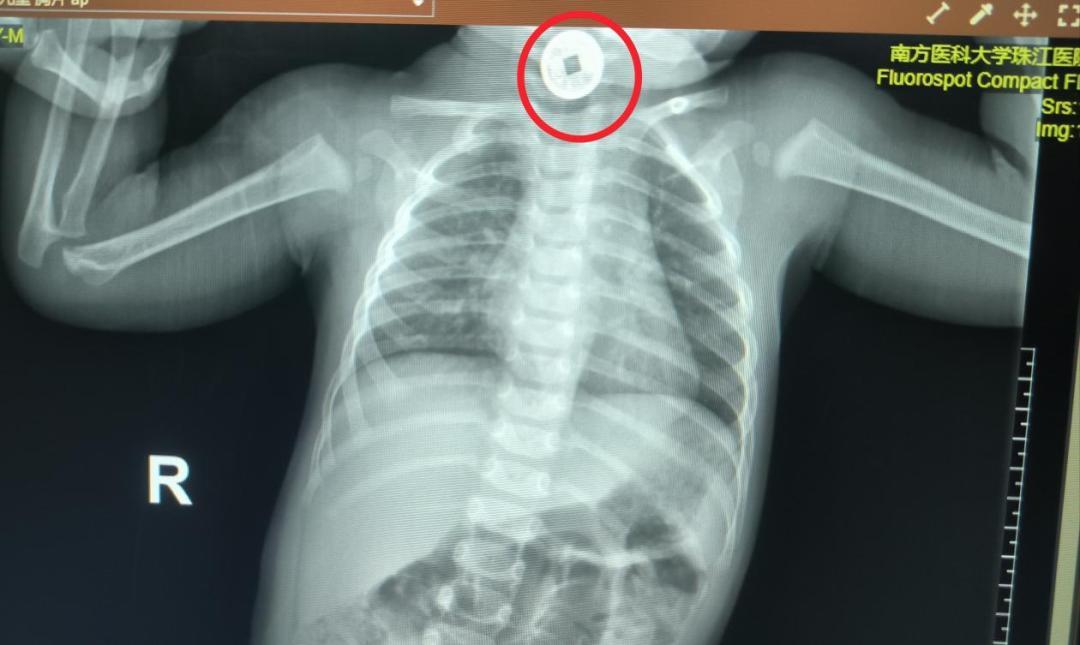

医护人员立刻启动紧急检查:通过影像学确认,一枚直径约2厘米的圆形祈福币卡在宝宝食道上段,距离咽喉仅3厘米。

这个位置很关键:食道上段狭窄,若异物滞留时间过长,可能压迫气管引发窒息,还可能损伤食道黏膜导致出血、感染。考虑到宝宝月龄小、配合度低,团队迅速制定了“全麻下食道镜异物取出术”方案。

手术中,陈帅君教授团队用特制的小儿异物钳小心固定祈福币,避开食道黏膜,仅用 2分钟就顺利将其取出。把钱币交到家长手中时,妈妈红着眼眶反复道谢。